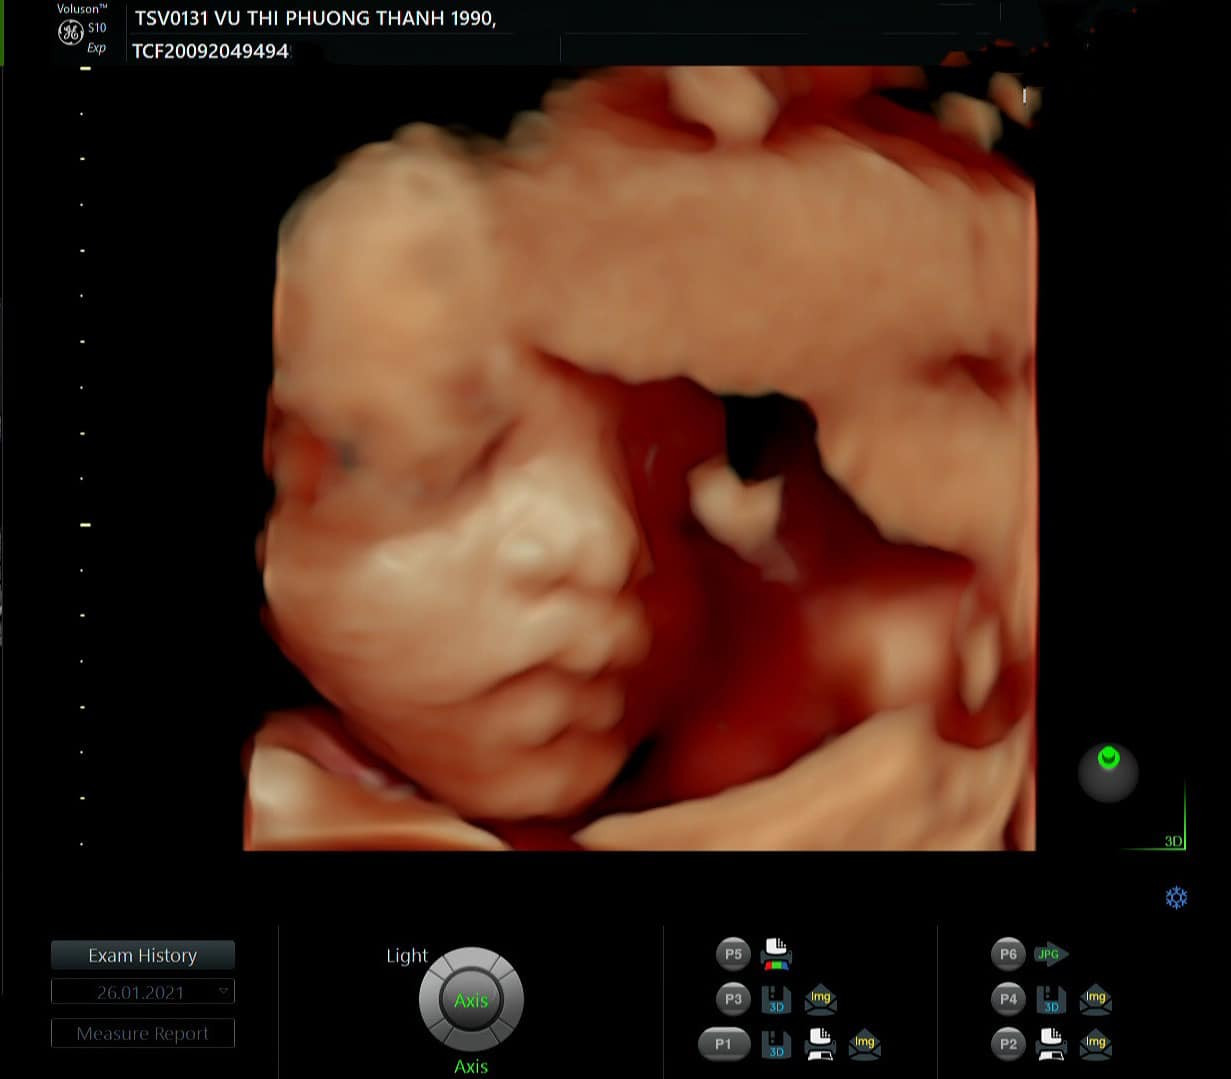

Trên trang cá nhân, Bảo Thanh viết: "Happy anniversary tui tặng ông món quà siêu to khổng lồ nhé chồng. Cô gái với khuôn mặt Vline và đôi môi trái tim của mẹ. Trộm vía em). Được biết đây là lần đầu Bảo Thanh chia sẻ hình ảnh công chúa nhỏ dễ thương. Dù chỉ nhìn qua hình siêu âm nhưng đôi môi trái tim và cằm Vline của em bé khiến khán giả đặc biệt dành lời khen dễ thương.